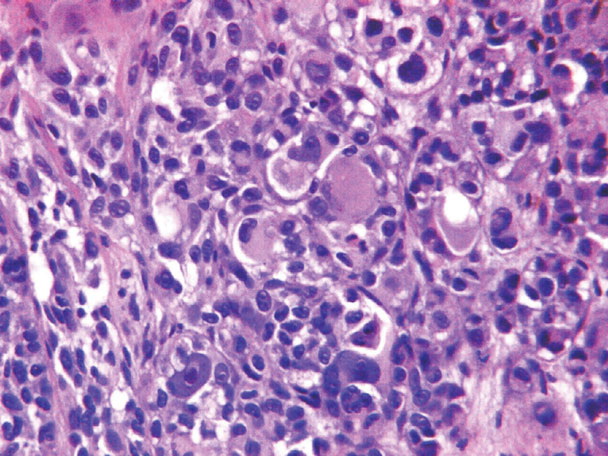

Pagetoid melanoma = الميلانوم الباجيتوئيدي